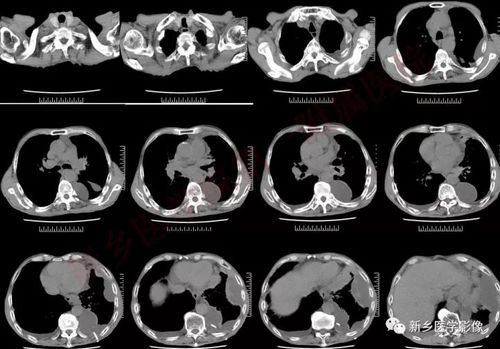

病例小细胞肺癌1例ct影像表现